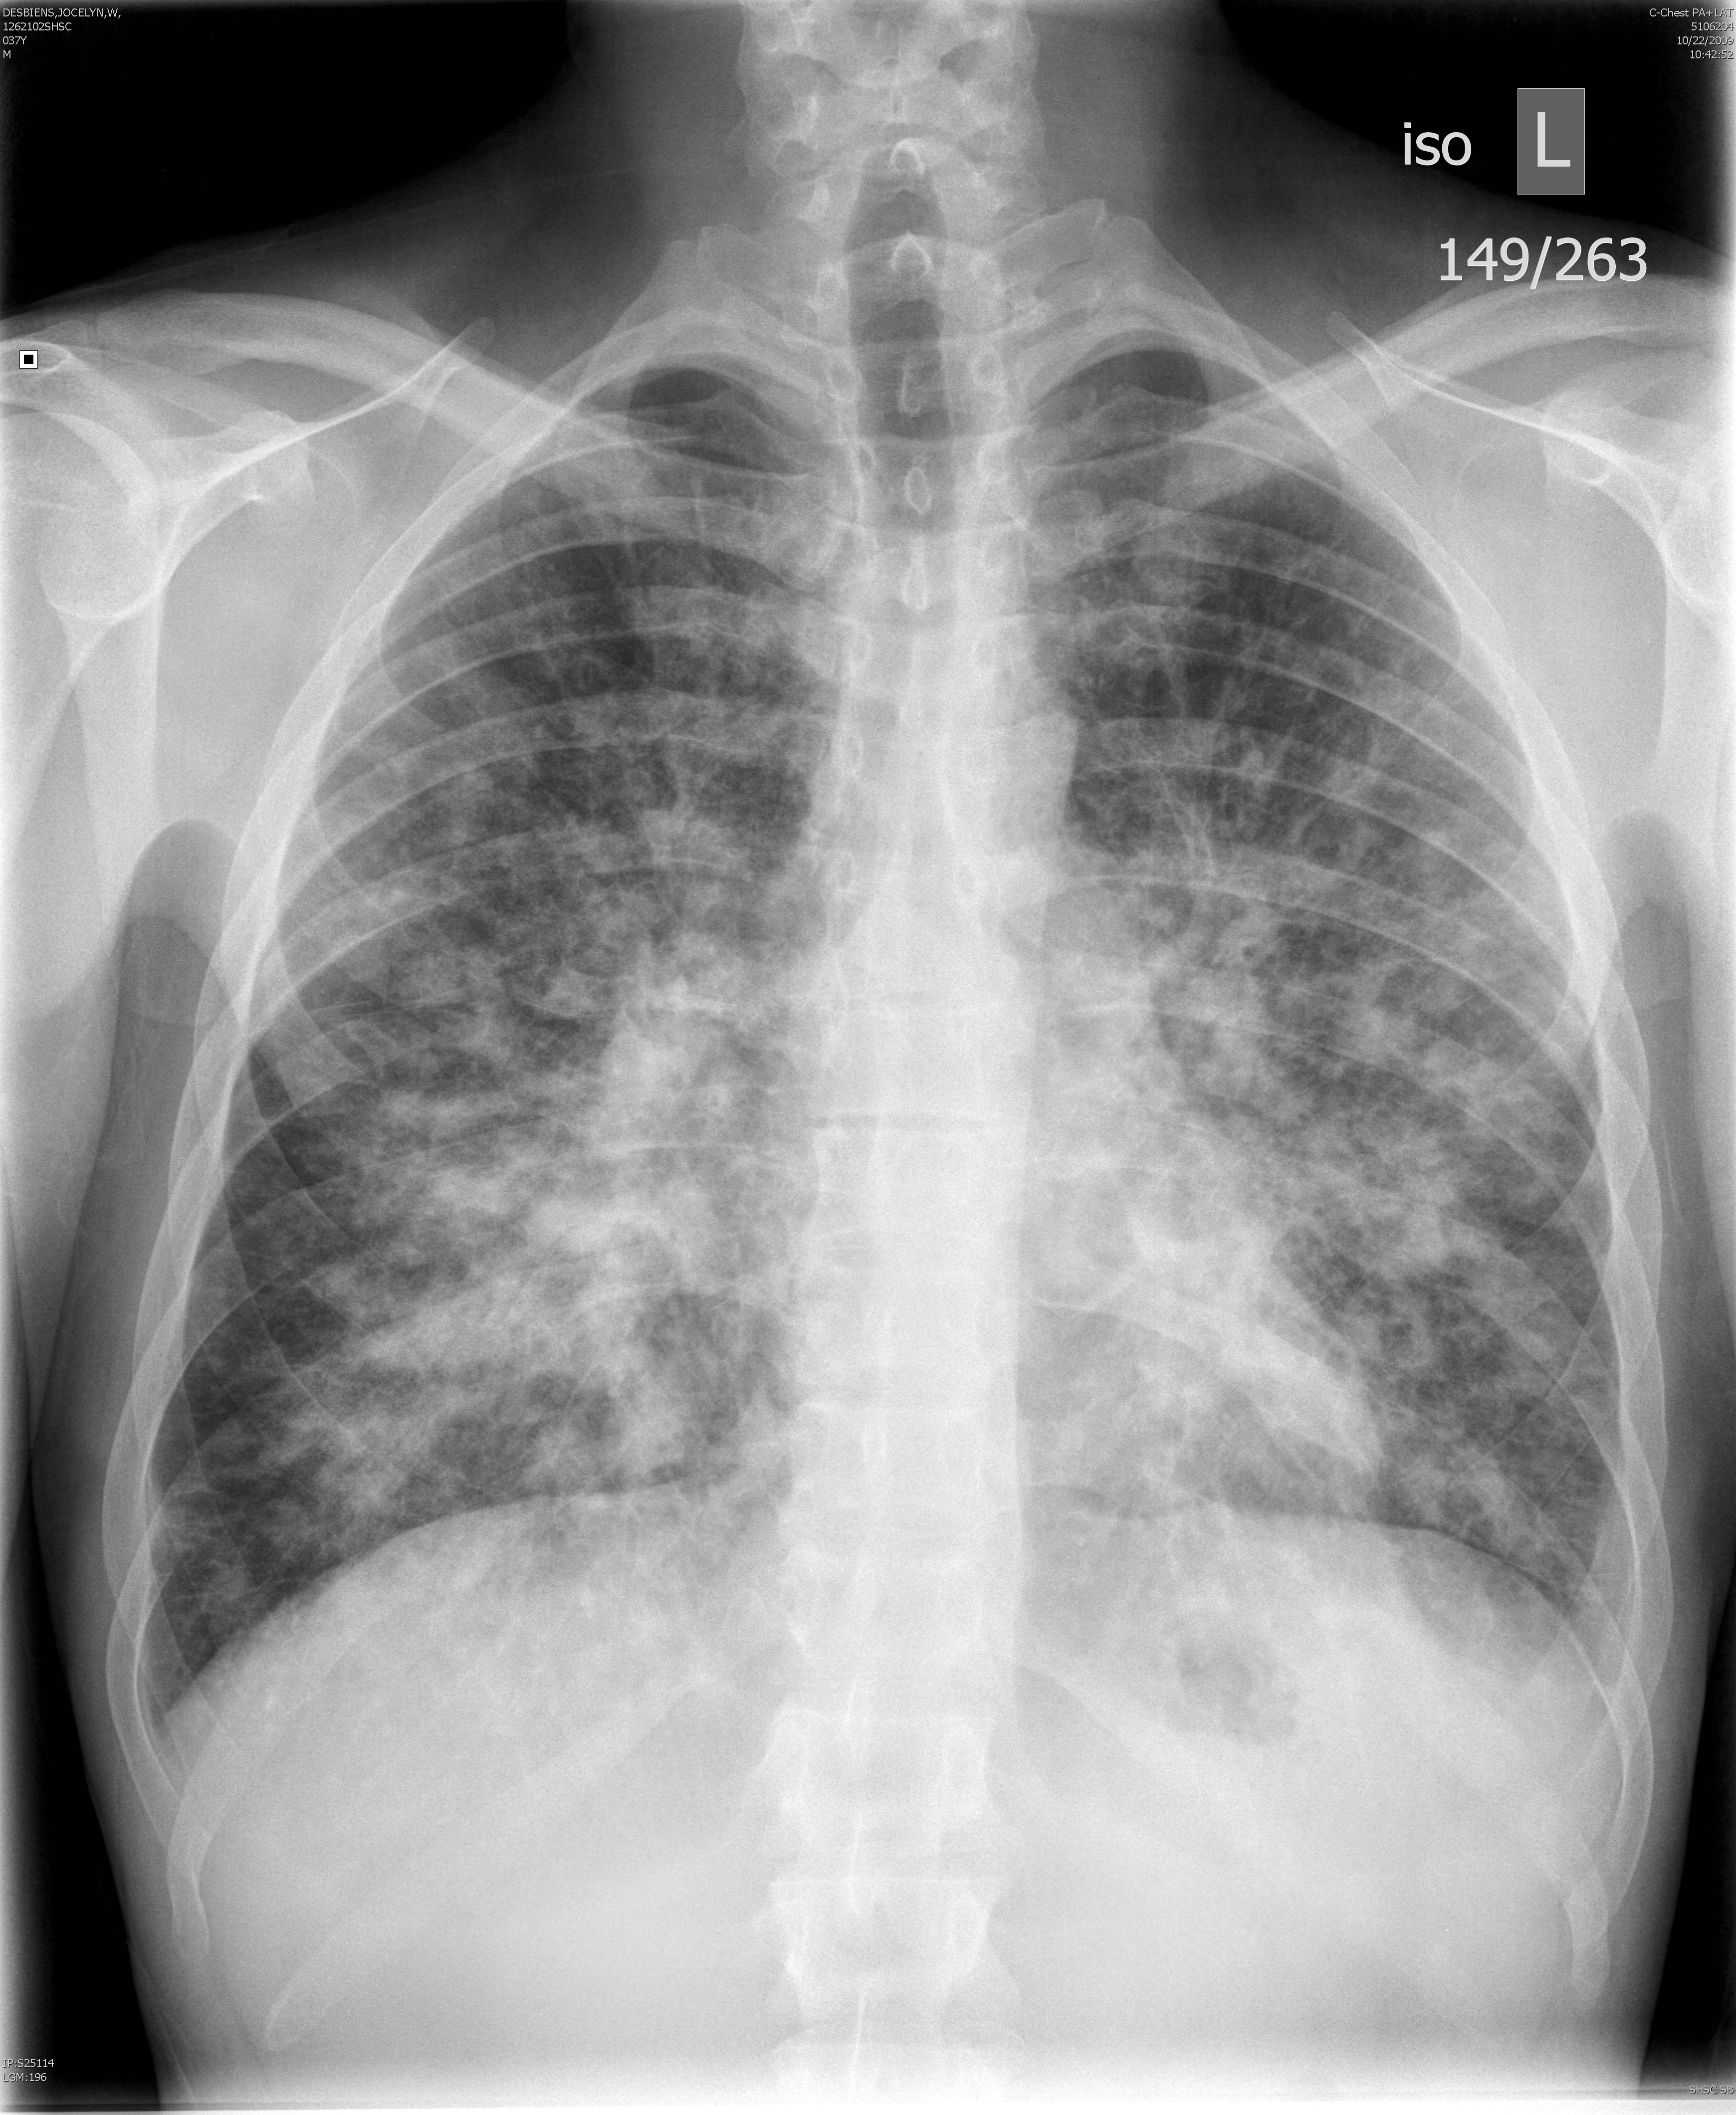

Gallery Lung Cancer Miscell KS PA

KS PA